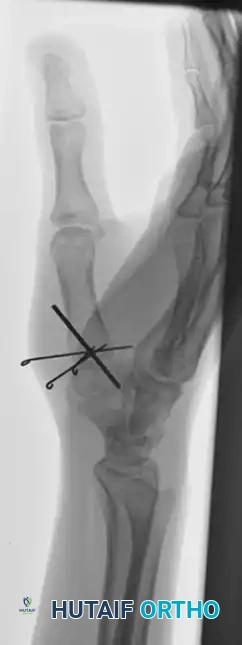

The following images detail the complex reconstruction, callus excision, and subsequent K-wire fixation required for delayed Bennett fracture presentations:

Consider a young man presenting with a 6-week-old Bennett fracture and an accompanying dorsal trapezial rim fracture. At this stage, the deforming forces have led to fixed malunion.

Surgical Approach for Delayed Union:

1. An open approach (Wagner or radiopalmar incision) is mandatory.

2. The CMC joint is exposed, and the organizing fracture callus is meticulously excised.

3. The fracture fragments are mobilized and anatomically reduced under direct vision.

4. Fixation is then achieved using the same pinning principles, driving K-wires across the joint to secure the reduction.